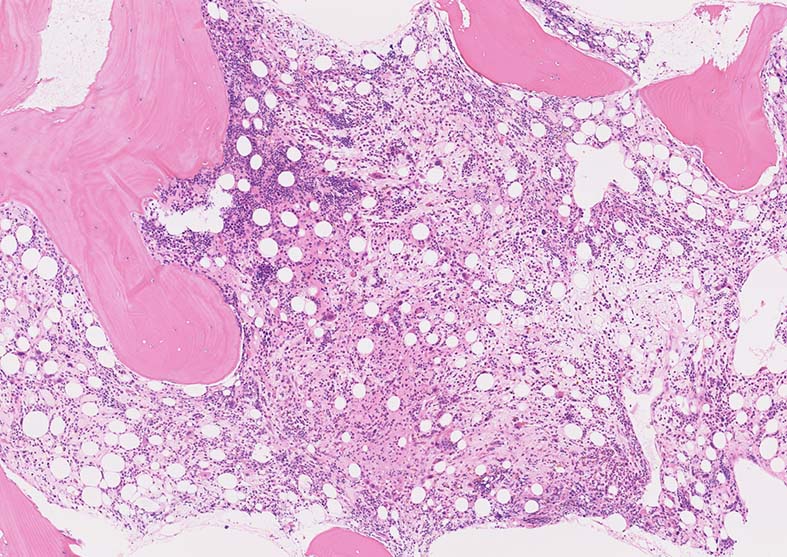

骨髄生検組織

1. 芽球増生の著明な髄様組織をしめすmegakaryoblastic leukaemia

2. 芽球の増殖が乏しく, myelofibrosisのみがめだつ2つのタイプがある。

骨髄生検組織: 骨梁は軽度に肥厚している. 明瞭な硬化像はない. 鍍銀染色でびまん性に線維増生が認められる.

AHEneu-OK.jpgBHEneu-hpf-OK.jpgCHE-oligo-hpf-OK.jpg

Bone marrow biopsy HE染色: A: 脂肪細胞は減少しているが線維化により造血細胞は疎になっている. B:小型Mgkが散在性に多数認められる.核は類円形, 小型低分葉の細胞が多く, 分離円形核をもつ異形成Mgkが出現している.

C:骨梁に沿って赤芽球が局在している. 通常は顆粒球系細胞が骨梁辺縁に局在する.

骨髄組織所見

正形成髄ないし過形成髄を呈する.

造血巣には, 巨核芽球と種々の成熟段階の異型巨核球が優位に増殖する. 両者の比率は症例によりさまざま.

小型巨核球が一様に増殖する症例では他のAML病型と形態的に区別ができないときがある.

巨核芽球とともに多数の成熟巨核球が増殖する症例もあるが, このときの成熟巨核球は一般に小型で, 低分葉核をもち異形成がめだつ.

微小巨核球が孤在性にあるいは集簇して多数認められる場合もある. クロマチンに濃染する1-2個の成熟核をもち成熟巨核球にみられる淡好酸性細胞質をわずかに有する細胞として見られる. 組織切片で巨核球系と同定するにはCD42b, CD61などの免疫染色が必要になる.

骨髄系, 赤芽球系の幼若細胞や異型細胞が混在することがあるが数はすくない.

骨髄線維症をともなうことがAML-M7の重要な特徴であるが, 必発ではない. 髄様の病変の症例がある.

弾性線維増殖であることが多いが, ところどころに膠原線維の増生を伴うことがある. (鍍銀染色, EVG, Azan染色で評価する)